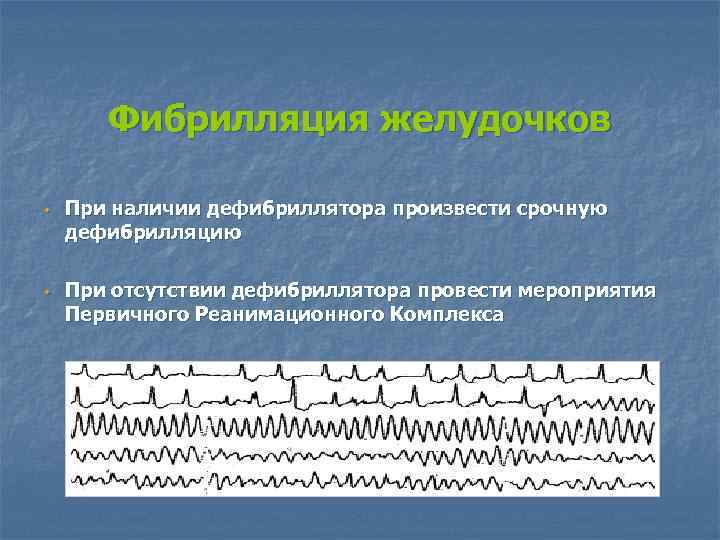

Фибрилляция желудочков w w При наличии дефибриллятора произвести срочную дефибрилляцию При отсутствии дефибриллятора провести мероприятия Первичного Реанимационного Комплекса